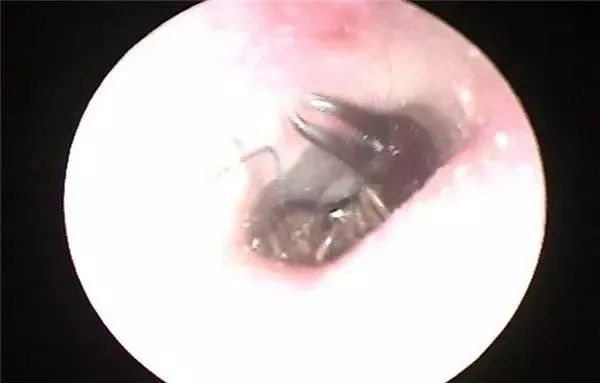

耳内镜检查图片

不料,她却在睡觉前突然感到头晕、头痛并伴有耳鸣。她强撑了一晚上,于6月29日上午10点来到医院就诊。常德市第三人民医院耳鼻喉科吴医生立即用耳内镜为其检查,发现李女士耳内竟然有只小虫,体积还不小,活的!

小虫蜷缩于鼓膜旁,四周还有点点虫卵或粪便样异物,耳壁皮肤破损明显……通过专用器械,吴医生轻轻将小虫取出,并用双氧水冲洗了耳道。